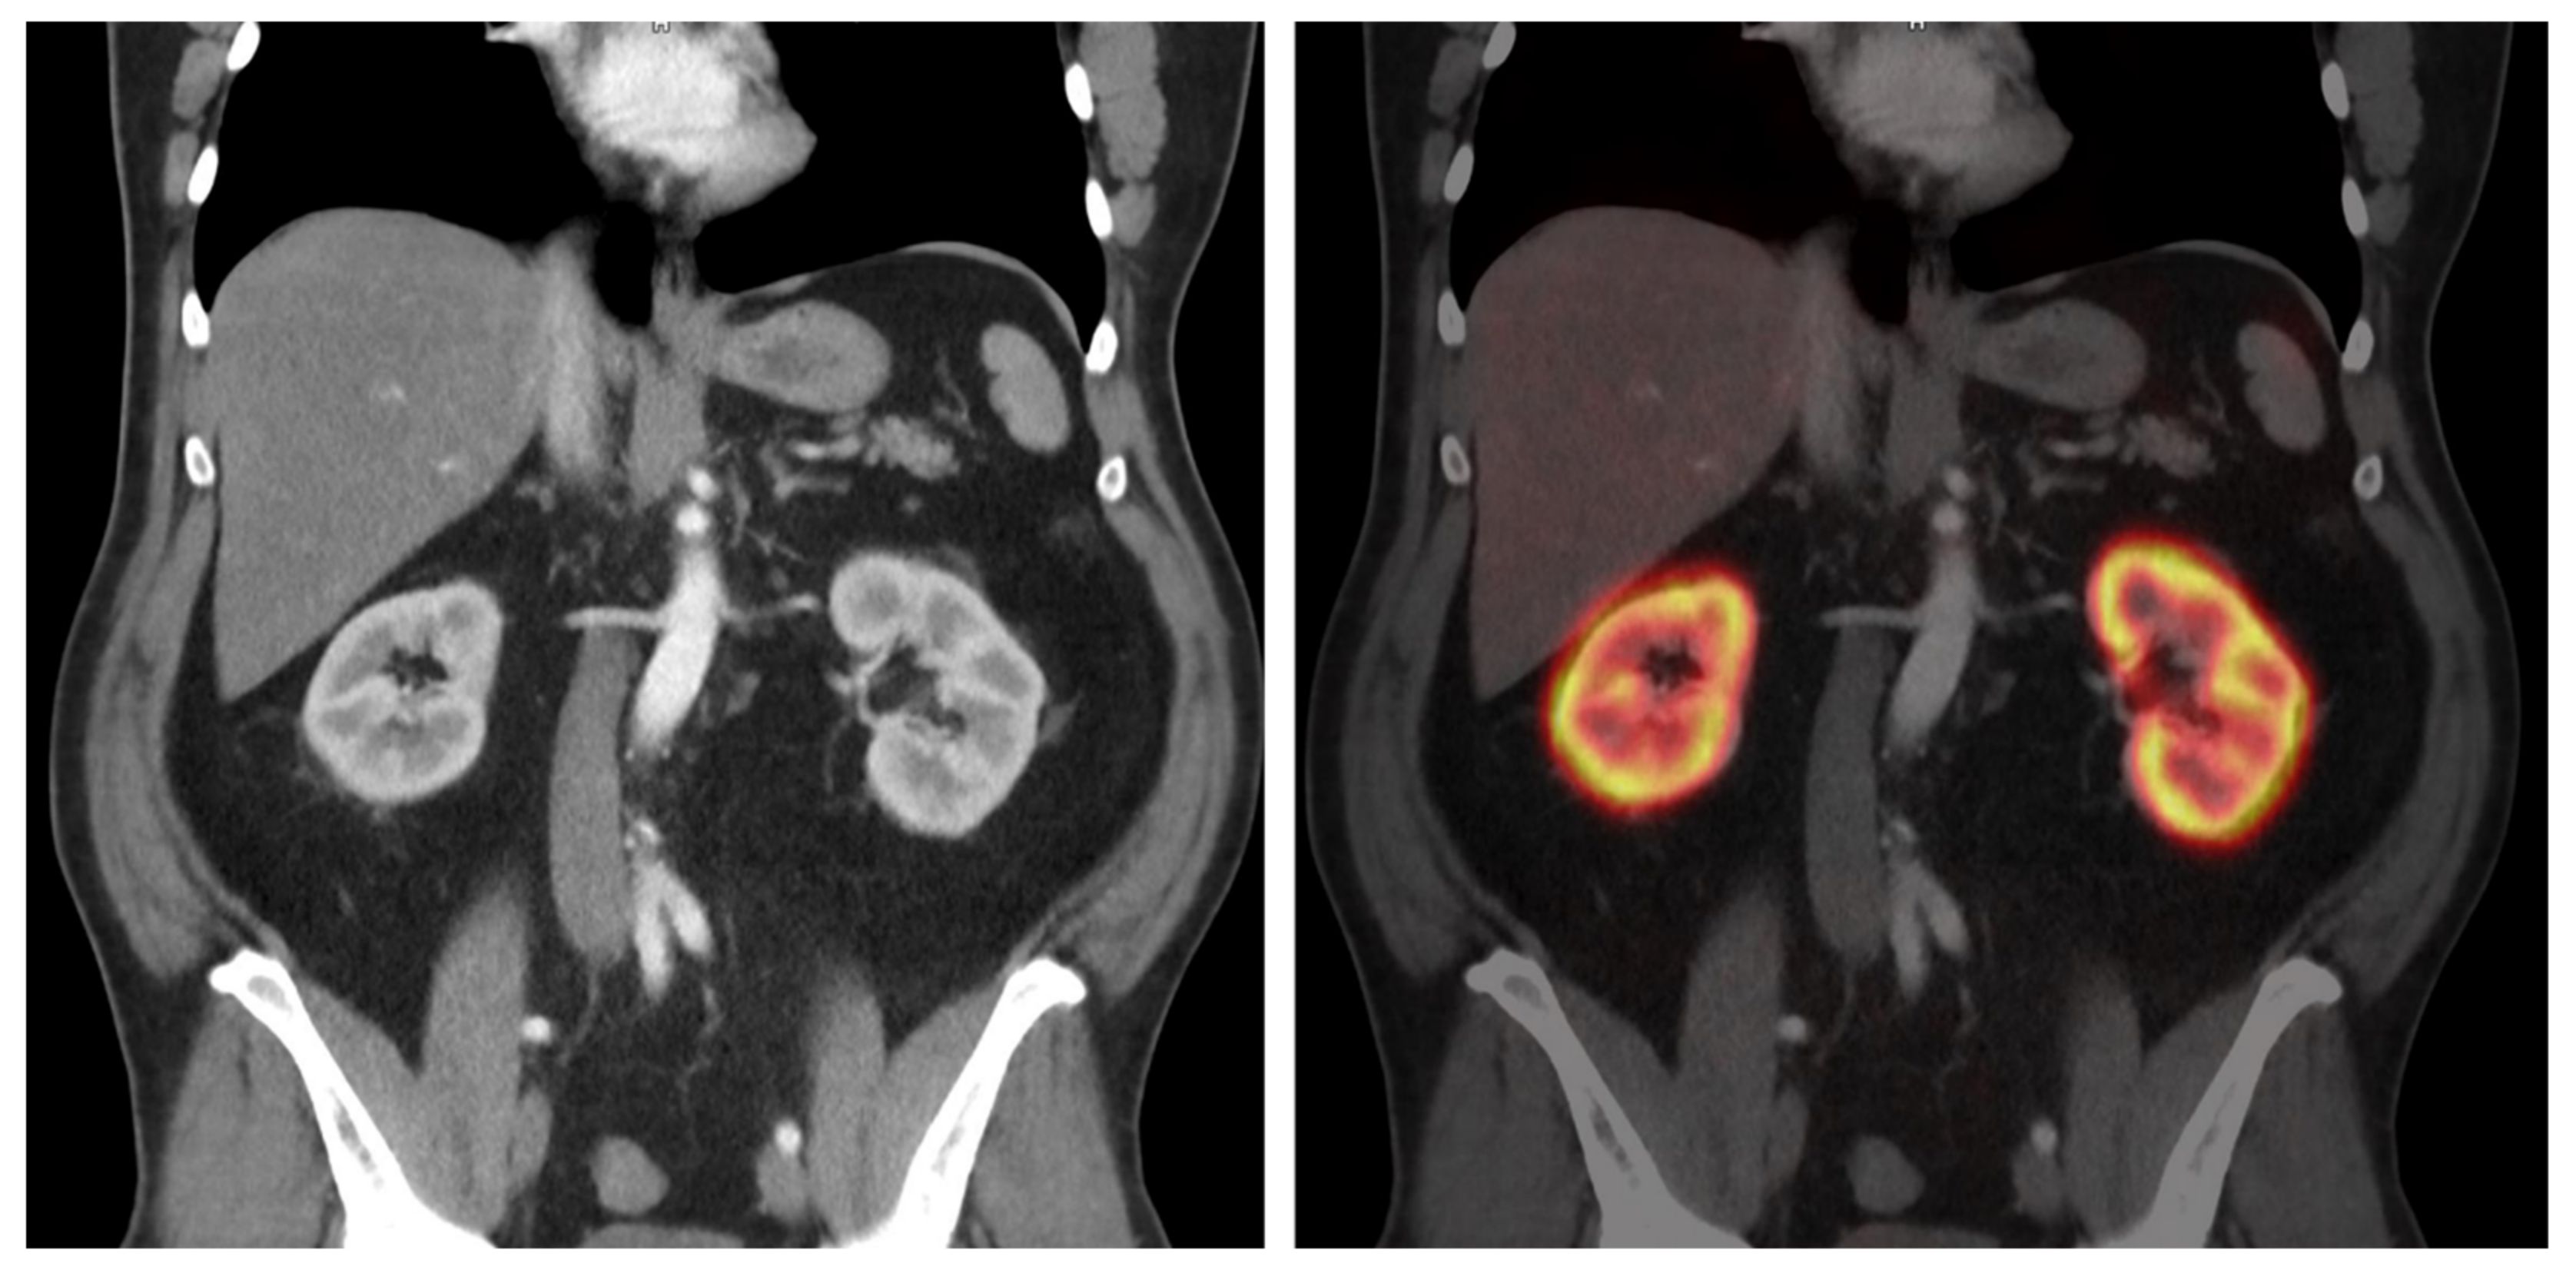

Dependence of Renal Uptake on Kidney Function in [68Ga]Ga-PSMA-11 PET/CT Imaging

2.4. Molecular Imaging Parameters Collected